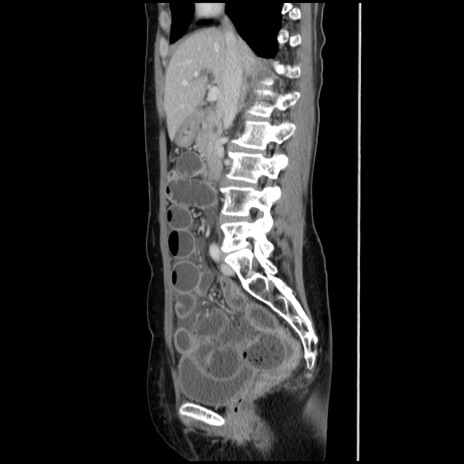

症例32(矢状断像)

【症例】40歳代 女性

【主訴】上腹部痛、嘔気・嘔吐

【現病歴】約9時間前頃から急に上腹部痛、嘔気、嘔吐が出現。改善しないため救急要請。

【既往歴】子宮頚癌(広汎子宮全摘術、放射線療法)、腸閉塞

【身体所見】腹部:平坦、軟、腸雑音亢進、上腹部を中心に腹部全体に圧痛あり。

【データ】WBC 8400、CRP 0.03